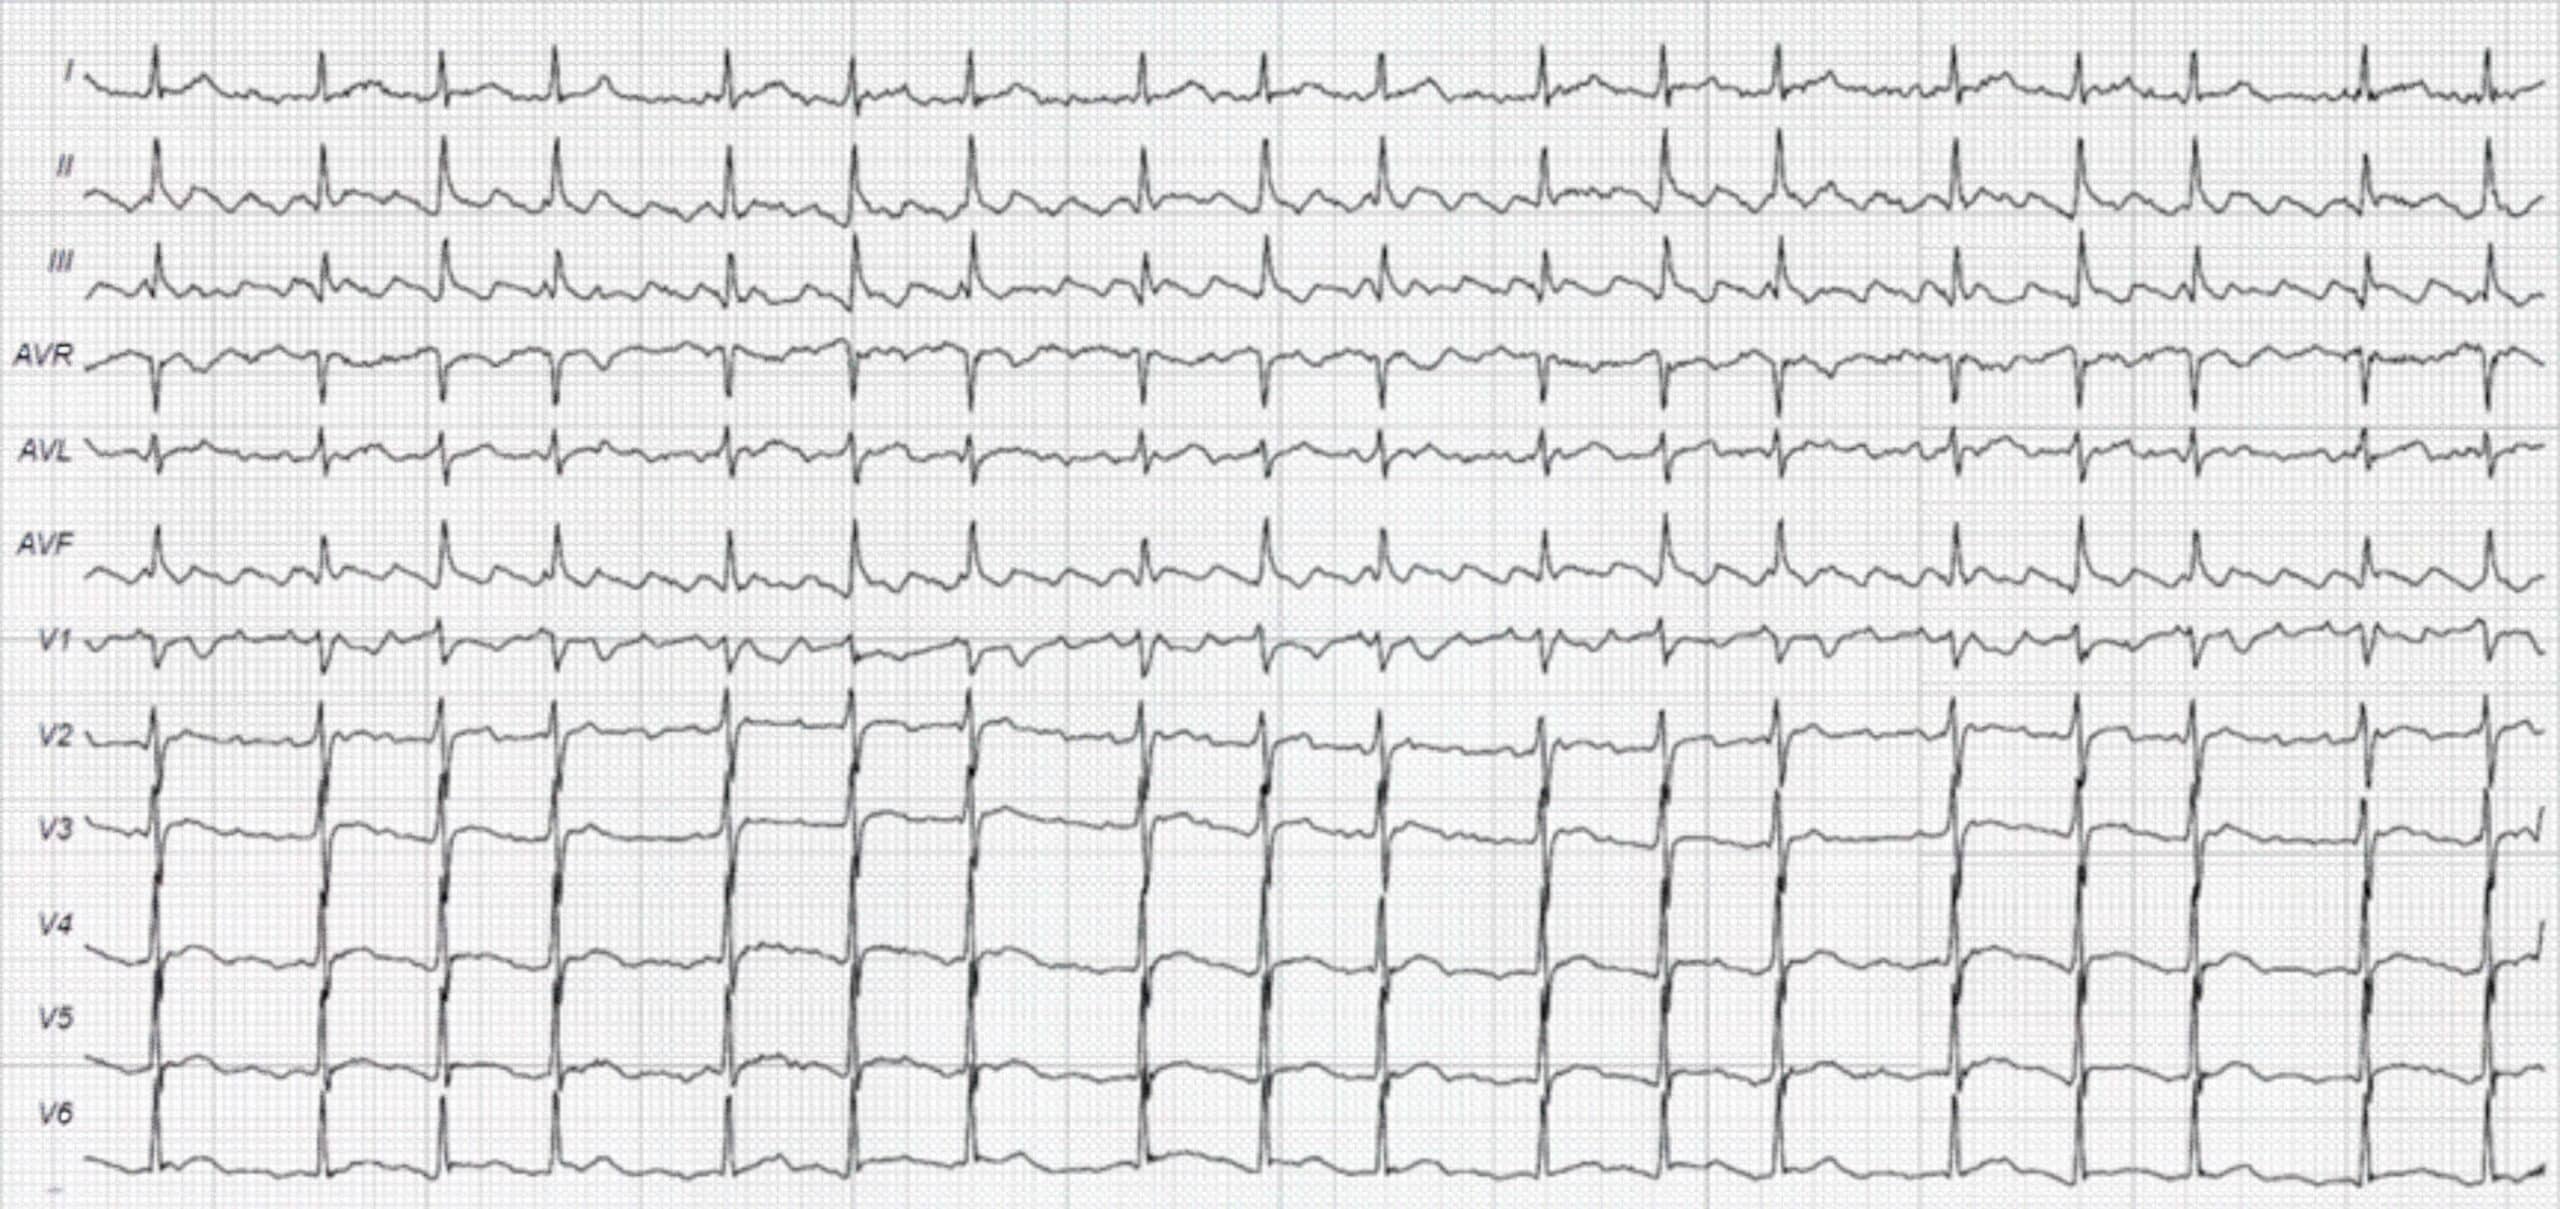

Uncommon Atrial Flutter ECG 34

In the ECG above (figure 4), there are no sawtooth waves appreciated in leads III and aVF. P waves are visible. However, limb lead II does have a sawtooth appearance typical of AFL. This represents a clockwise reentry circuit, an uncommon variant.

34 Burns E. Atrial flutter. Life in the fastlane website. Accessed September 4, 2020.

https://litfl.com/wp-content/uploads/2018/08/ECG-Atrial-Flutter-variable-block-2-1-4-1.jpg